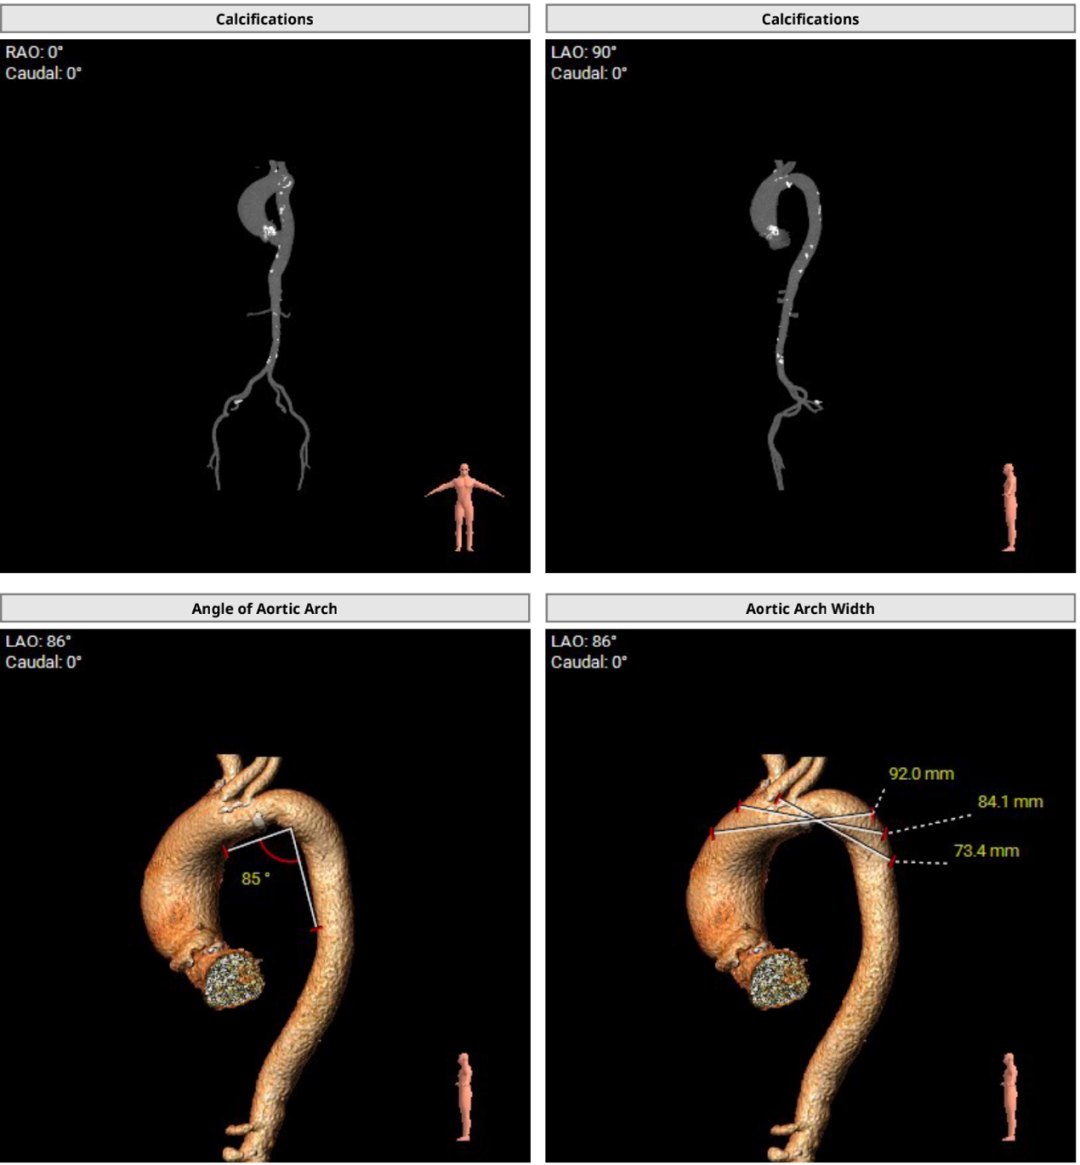

4.主动脉瓣环与水平面夹角为62°,横位心,主动脉弓部夹角,弓距尚可;

5.主动脉弓、腹主动脉可见散在斑块,股动脉穿刺处未见钙化、狭窄,入路血管直径尚可。

4.横位心,主动脉弓距及夹角尚可,升主动脉扩张,警惕血管夹层、破裂等风险;综合预估输送系统过 弓难度适中,跨瓣难度适中,必要时辅助以snare过弓跨瓣;

随着TAVR技术在国内的普及,主动脉瓣狭窄患者有了更多的治疗选择。本例患者为主动脉瓣重度狭窄伴轻度反流,患者伴代偿性心力衰竭,术前评估适宜行TAVR手术,有TAVR手术指征。术前CT分析提示患者为Type0型二叶式主动脉瓣,瓣环径23.5mm,瓣叶增厚伴重度钙化,钙化主要分布于无窦与左窦交合缘及瓣叶边缘,LVOT呈类直筒状形态,预估人工瓣膜会有较明显形变,有根部撕裂、损伤风险。左室流出道可提供辅助锚定,综合预估瓣膜锚定定位精度要求较高。患者又为横位心,主动脉弓距及夹角尚可,升主动脉扩张,需警惕血管夹层、破裂等风险,对经导管主动脉瓣输送系统过弓、跨瓣的性能要求较高。综合以上因素,该患者行TAVR手术对术者快速、精准的操作能力及手术团队的密切配合要求较高。广东省人民医院赣州医院(赣州市立医院)倪忠涵院长带领团队,经过心内科、心外科、麻醉科、超声等多学科团队的缜密讨论,最终决定为患者施行TAVR手术治疗。